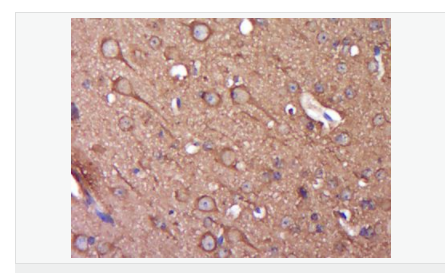

Synuclein 包括α-Synuclein,β-Synuclein 和γ-Synuclein 是神經(jīng)細(xì)胞中富含的前突觸蛋白。α-Synuclein,Alzheimer’(AD)病淀粉樣蛋白沉積的成份之一,集中分布在神經(jīng)細(xì)胞的包體和突觸。在帕金森病人中發(fā)現(xiàn)有α-Synuclein的變異型,而γ-Synuclein與軸突病理學(xué)有關(guān)。此抗體將為Lewy小體癡呆癥、Parkinson癥、AD和其它一些神經(jīng)性疾病提供有用的病理診斷。